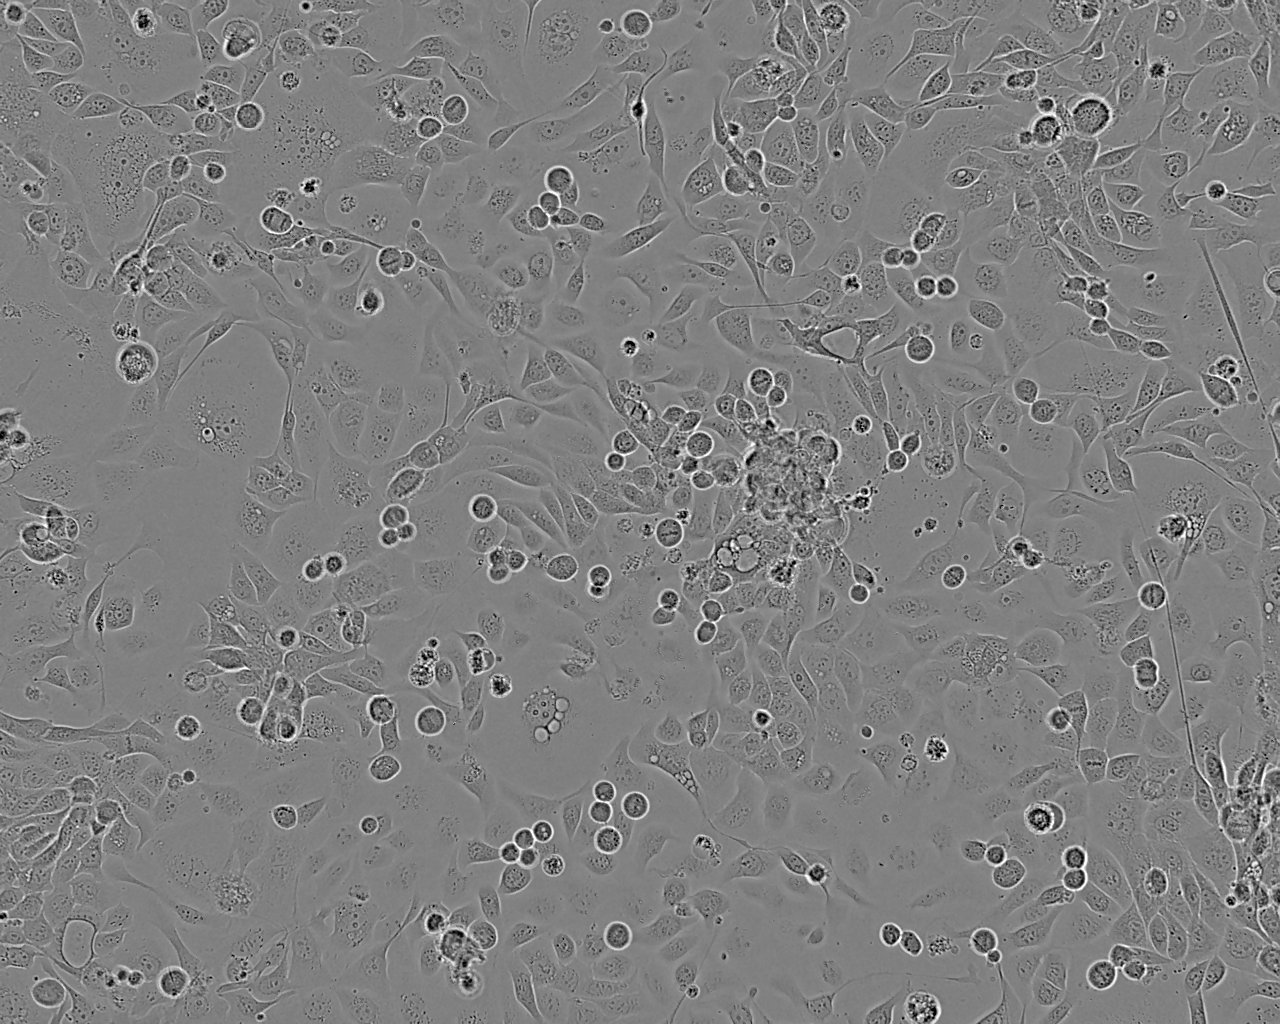

Derived from the pleural effusion of a 62-year-old Caucasian male. The cells are tumorigenic in nude mice.

Cell Type

Subculture Routine

Split sub-confluent cultures (70-80%) 1:3 to 1:6 i.e. seeding at 2-4x10,000 cells/cm² using 0.05% trypsin/EDTA; 5% CO₂; 37°C.

Culture Medium

RPMI 1640 + 2mM Glutamine + 10% Foetal Bovine Serum (FBS).

Growth Mode